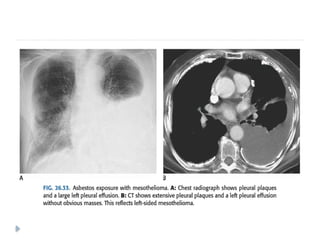

MALIGNANT MESOTHELIOMA

⚫ Associated with asbestos exposure, with an average latency of

On imaging :

⚫ Diffuse nodular pleural thickening – pleura along the

intercostal spaces, costophrenic angles and lung apices

are involved.

⚫ Pleural plaques (latent period of formation is 20yrs; strong

indicator of asbestos exposure): usually seen adjacent to ribs.

Involving sixth to ninth rib. These themselves are not

premalignant

⚫ Pleural effusion

⚫ Calcifications may be seen along diaphragmatic pleura.